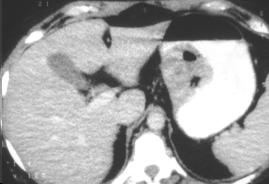

Leiomyome de la petit coubure avec

image ulceree a la surface . Image TDM en coupe

axiale a ingestion baryte . |